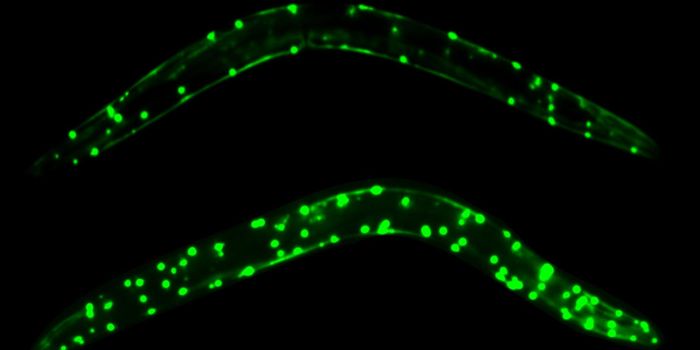

In this video, you can see a 2017 Koch Institute Image Award winner, "Body of Knowledge." This research is part of the D

...

Written By:

Carmen Leitch